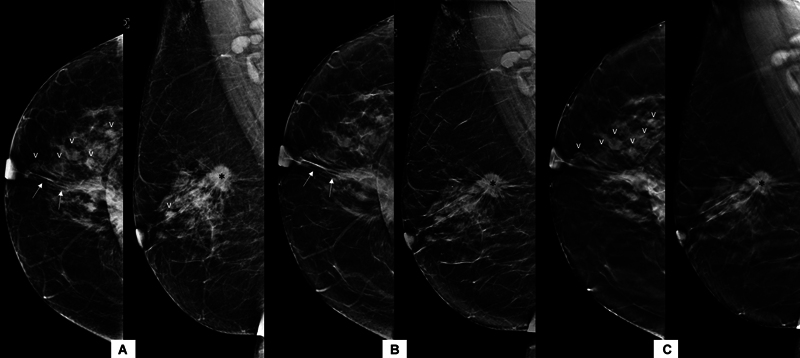

合成乳房x线摄影(SM)是指从数字乳房断层合成(DBT)数据中获得的二维(2D)图像。与传统的全视野数字乳房x线摄影(FFDM)加断层合成相比,它可以减少辐射剂量和扫描时间。目的比较二维FFDM与DBT合成乳房x线照片在诊断人群中的诊断效果。材料与方法经研究所伦理委员会批准,在2年内共获得1468张含FFDM和SM + DBT的乳房x线照片并进行分析。根据2013年美国放射学会乳腺成像报告和数据系统(BI-RADS)词汇,对图像进行报告和比较,包括乳房密度、肿块形态学特征、钙化、不对称或结构扭曲的存在,然后进行BI-RADS分类。采用Kappa值研究两种模式之间的一致性,并记录两组的辐射暴露剂量。结果FFDM和SM + DBT在乳腺密度、肿块特征和钙化检测方面具有很强的一致性(kappa >.8)。SM + DBT对乳腺密度和肿块密度的分期下降无统计学差异。SM组乳头乳晕复合体的可视化较差(50.34% vs. 76.29%),且存在SM特异性伪影,主要与重建算法有关。SM的辐射剂量较高。结论FFDM与SM + DBT诊断效果相当。后者可能对乳房致密的患者特别有用。

Background  Synthesized mammography (SM) refers to two-dimensional (2D) images derived from the digital breast tomosynthesis (DBT) data. It can reduce the radiation dose and scan duration when compared with conventional full-field digital mammography (FFDM) plus tomosynthesis. Purpose  To compare the diagnostic performance of 2D FFDM with synthetic mammograms obtained from DBT in a diagnostic population. Materials and Methods  A total of 1,468 mammograms with both FFDM and SM + DBT images were obtained and analyzed over 2 years, after obtaining approval from the institute ethics committee. The images were reported and compared as per the 2013 American College of Radiology Breast Imaging Reporting and Data System (BI-RADS) lexicon in terms of breast density, morphological features of mass, calcifications, and presence of asymmetry or architectural distortion followed by the BI-RADS category. The agreement between the two modalities was studied using the Kappa value, and the radiation exposure dose was recorded in both groups. Results  FFDM and SM + DBT showed strong agreement for breast density, mass characteristics, and detection of calcifications (kappa > 0.8). Downstaging of breast density and mass density were seen by SM + DBT without any statistically significant difference. The nipple-areola complex visualization was poor in SM (50.34 vs. 76.29% in FFDM), and there were SM-specific artifacts mainly related to the reconstruction algorithm. The radiation dose was higher with SM. Conclusion  FFDM has comparable performance to SM + DBT in diagnostic setup. The latter may be particularly helpful in patients with dense breasts.